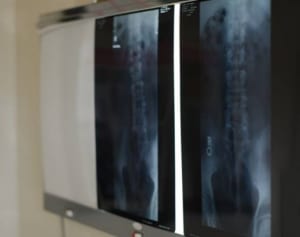

1カ月ぶんの便がレントゲンに…「便秘」患者語る原因と治療

2018/02/15 11:00人知れず“お通じ”のことで悩みを抱える人は推定で1,000万人いるとみられている。これまで日本では、便秘は病気とはみなされず、医療機関に相談しても効果的な治療がなされないことが多々あった。自己診断で市販薬に頼って“下痢と便秘”を繰り返して症状を悪化させる人、あるいは、便秘の原因となる深刻な病気を見逃してしまう人までいるという。「ただの便秘と思って放っておくのは危険です。大腸がんなどの病気や薬の副作 -